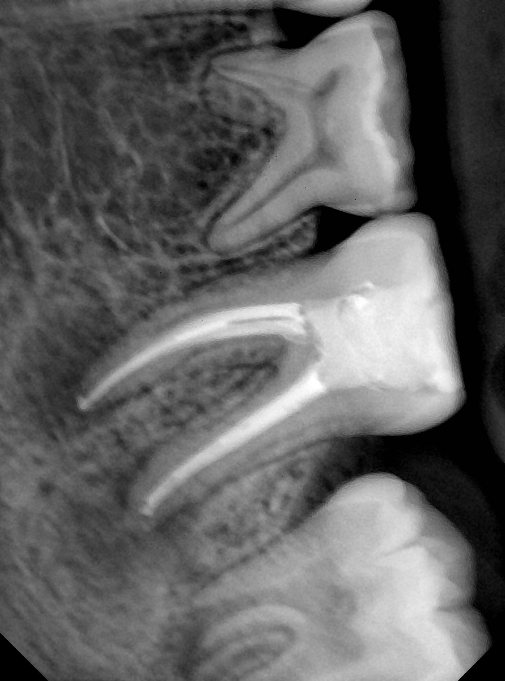

CR/DR 牙齿分割阶段记录

当前进展

- 完成了 CR/DR 牙齿相关分割训练

- 当前结果已经达到阶段预期,但仍有细节问题需要继续处理

相关测试

遇到的问题

- 训练过程中出现过 mask 下移问题

- 部分结果会出现 box 填充异常

- mask 边缘仍然有比较明显的锯齿感